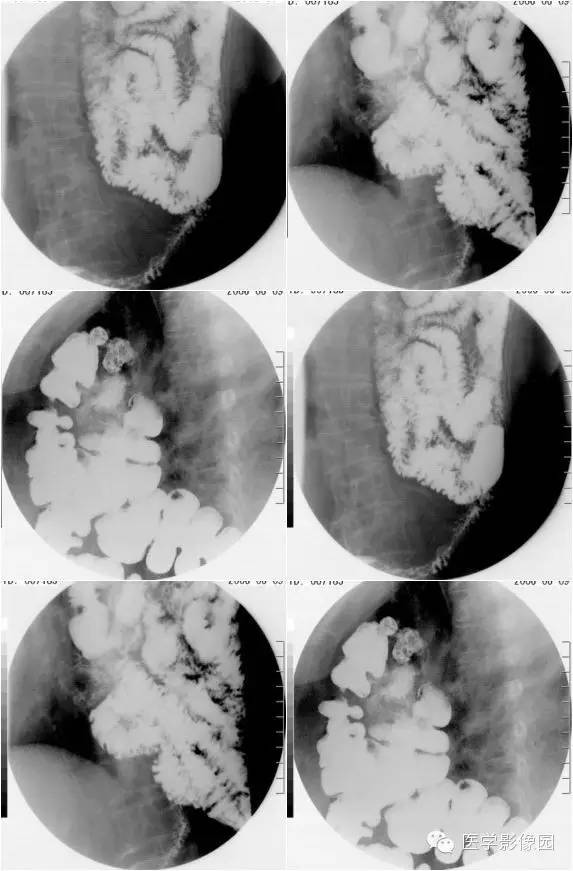

膈疝1例X线及CT影像表现

膈疝的形成除先天性膈肌融合部缺损和薄弱点外,还与下列因素有关:

①胸腹腔内的压力差异和腹内脏器的活动度;各种引起腹内压力增高的因素如弯腰、排便困难和怀孕等均可促使腹内脏器经膈肌缺损和薄弱部进入胸内。

②随着年龄增长,膈肌肌张力减退和食管韧带松弛,使食管裂孔扩大,贲站或胃体可以经过扩大的食管裂孔突入后纵隔。

③胸部外伤尤其胸腹联合伤引起膈肌破裂。